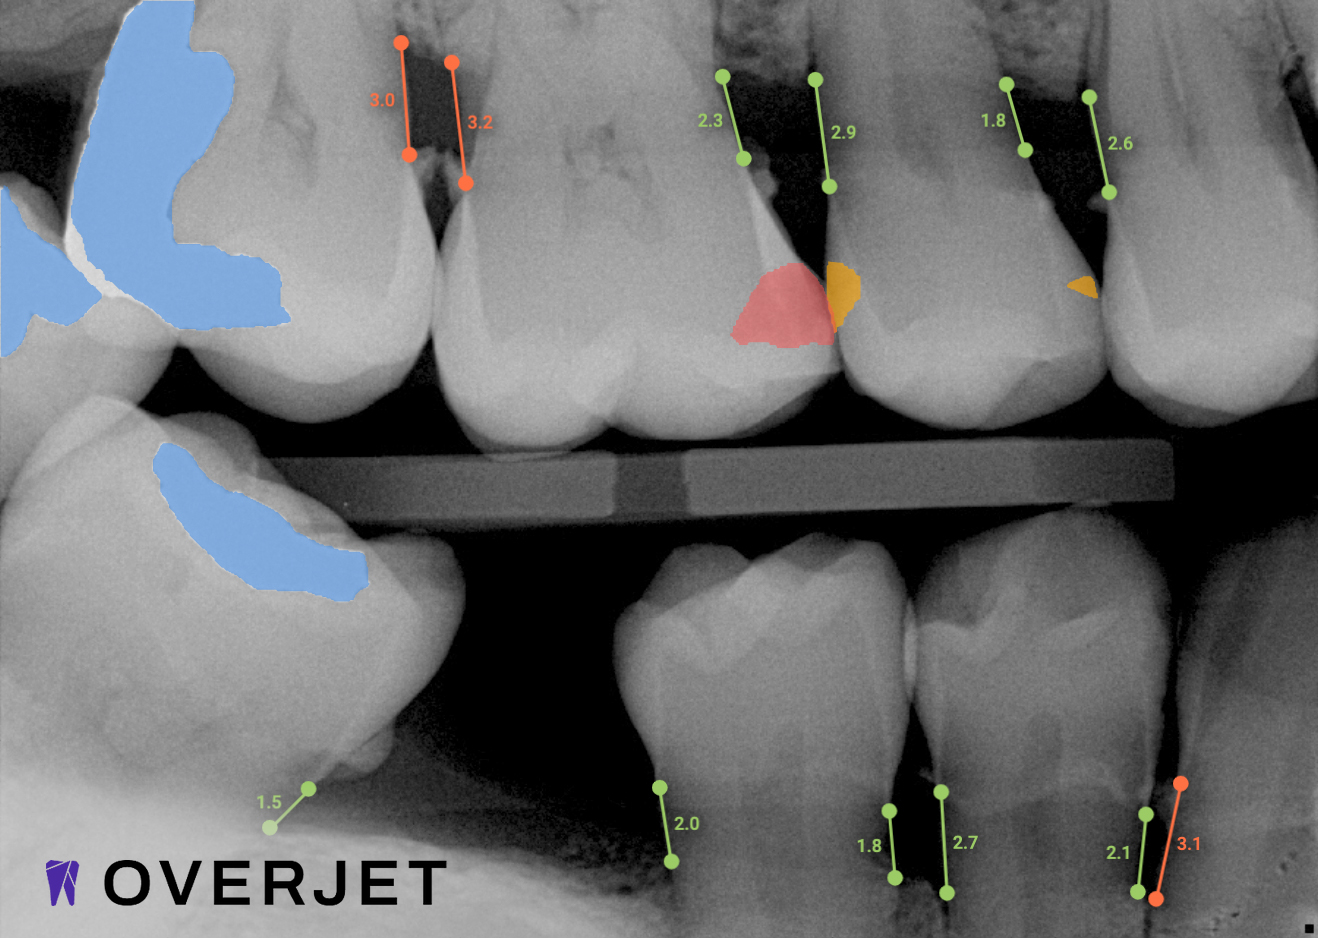

See More with AI

Overjet’s artificial intelligence technology transforms traditional black-and-white X-rays by adding a layer of data that instantly outlines decay (cavities) and measures bone loss. This makes it easy for you to see your results alongside your dentist.  It’s like getting a second opinion delivered instantly. With Overjet’s analysis and easy-to-read presentation, you will have the information you need to make an informed decision about your oral health. Together, we’ll review your findings and discuss the best steps to take to achieve your goals.